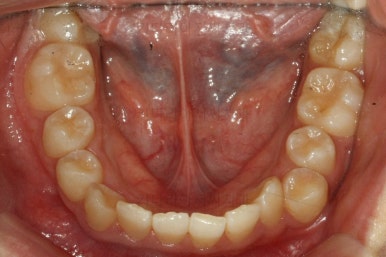

마찬가지로 부산교정치과 키다리아저씨치과에 처음 내원하셨을 당시의 입안 모습입니다.

또 다른 문제는 위아래 앞니가 매우 많이 겹쳐져 있어서 아래 앞니가 거의 보이지 않는다는 점입니다.

작은 앞니가 왜소치이다 보니 윗니에는 틈이 남아있고 교합도 조금 엉성한 모습이에요.

왜소치의 사이즈가 위아래 교합을 맞춰주는데 방해가 된다고 판단하여 왜소치를 크게 해주기로 결정했습니다.